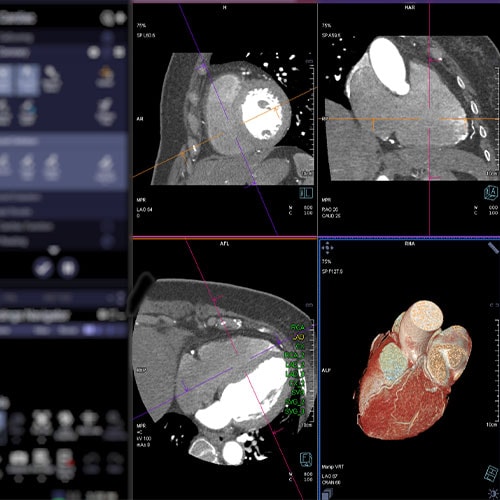

DPC et JESFC